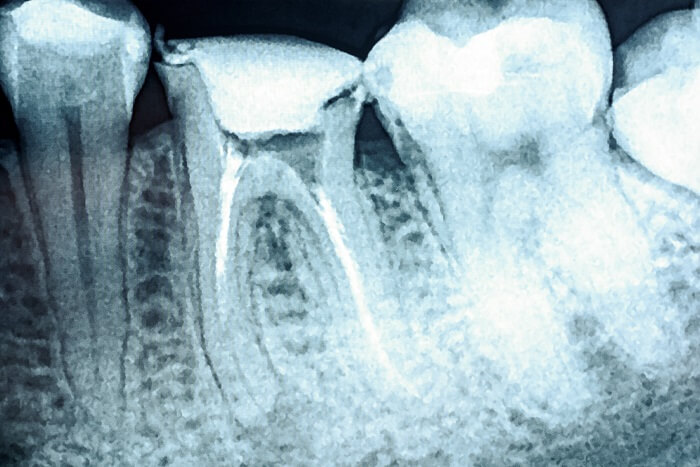

A classificação de Vertucci é um dos tantos modelos que buscam classificar a anatomia do sistema de canais radiculares. Ela foi criada em 1984 com o objetivo de enquadrar os tipos anatômicos dentais internos.

Se você já frequenta as suas primeiras aulas de endo, é bem provável que esteja começando a estudar essa classificação, que é fundamental para compreender a existência de diferentes tipos de canais articulares. Além disso, é importante destacar que muitos profissionais não têm sucesso nos procedimentos pela falta de conhecimento sobre as variações anatômicas dessa área.

Como explicamos, a classificação de Vertucci é categorizada em oito tipos. Confira a explicação do artigo “Métodos de visualização para identificação do segundo canal da raiz mesiovestibular de molares superiores” no resumo abaixo.

| Tipo I | Um único canal estende-se a partir da câmara pulpar para o ápice. |

| Tipo II | Dois canais separados deixam a câmara pulpar e unem-se no ápice para formar um canal. |

| Tipo III | Um canal deixa a câmara pulpar, se divide em dois dentro da raiz e, em seguida, se transforma em um canal. |

| Tipo IV | Dois canais separados e distintos estendem-se da câmara pulpar até o ápice. |

| Tipo V | Um canal deixa a câmara pulpar e se divide aquém do ápice em dois canais distintos com forame apical separado. |

| Tipo VI | Dois canais separados deixam a câmara pulpar, fundem-se no corpo da raiz, e se dividem no ápice para sair como dois canais distintos. |

| Tipo VII | Um canal deixa a câmara pulpar e, em seguida, divide-se e reencontra-se dentro do corpo da raiz, e divide-se em dois canais curtos e distintos no ápice. |

| Tipo VIII | Três canais separados e distintos estendem-se desde a câmara pulpar com o ápice. |